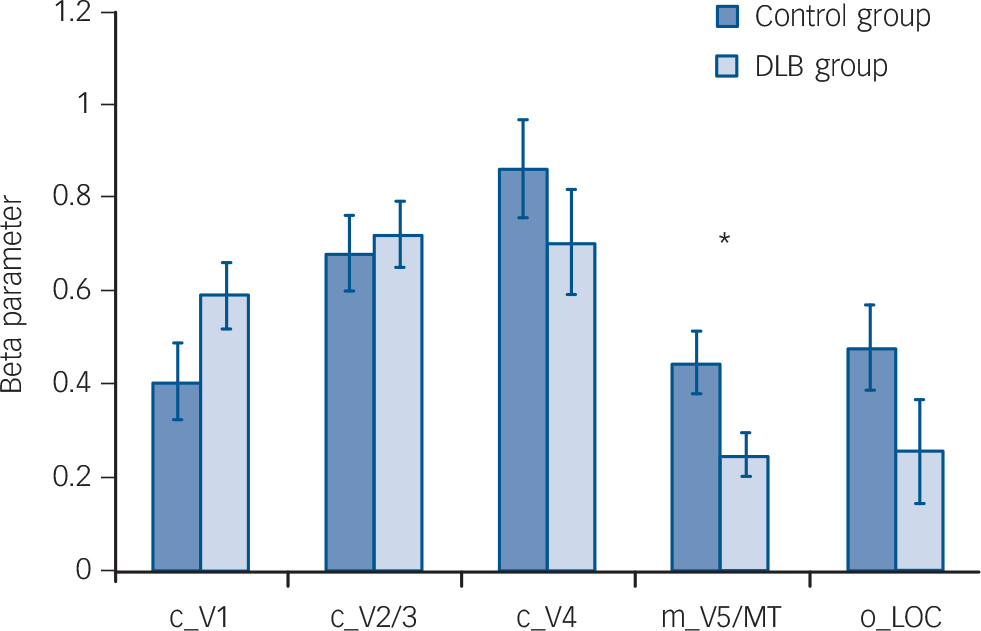

Whole brain analyses comparing groups, however, did not demonstrate any significant differences in activation between DLB and control groups for each of the tasks. Region of interest analysis (Fig. 2) for lower visual areas confirmed this finding, with no differences in activity between the control and DLB groups for checkerboard stimulus (V1 ROI) or objects stimulus analyses (LOC ROI). However, the ROI localised on the V5/MT showed that the DLB group had reduced activation to the motion stimulus in this area compared with controls (P = 0.02). The results of the exploratory analyses of BOLD activity in the other ROIs for each of the tasks are shown in online Table DS1. Of note, there were no significant differences between DLB and control groups in the BOLD response to the three visual stimuli in V1, V2/3 or V4.

not significant in V1 (P =0.25) or V2/3 (P = 0.19), but approached significance in V4 (P = 0.08). The reduction was

Fig. 2 Bar chart showing region of interest (ROI) analysis comparing control group v. dementia with Lewy bodies (DLB) group with regard to functional BOLD activations to different visual stimuli (mean (s.e.)).

c_V1, checkerboard activation in V1 ROI; c_V2/3, checkerboard activation in V2/3 ROI; c_V4, checkerboard activation in V4 ROI; m_V5/MT, motion activation in ROI V5/MT; o_LOC, objects activation in ROI lateral occipital complex; BOLD, blood oxygen-level dependent. There were no significant differences between groups for ROI activations except for motion stimulus contrast (P = 0.02). *P<0.05.

significant in: V5/MT, P = 0.05; LOC, P = 0.05; precuneus, P<0.001; SLO, P = 0.004.